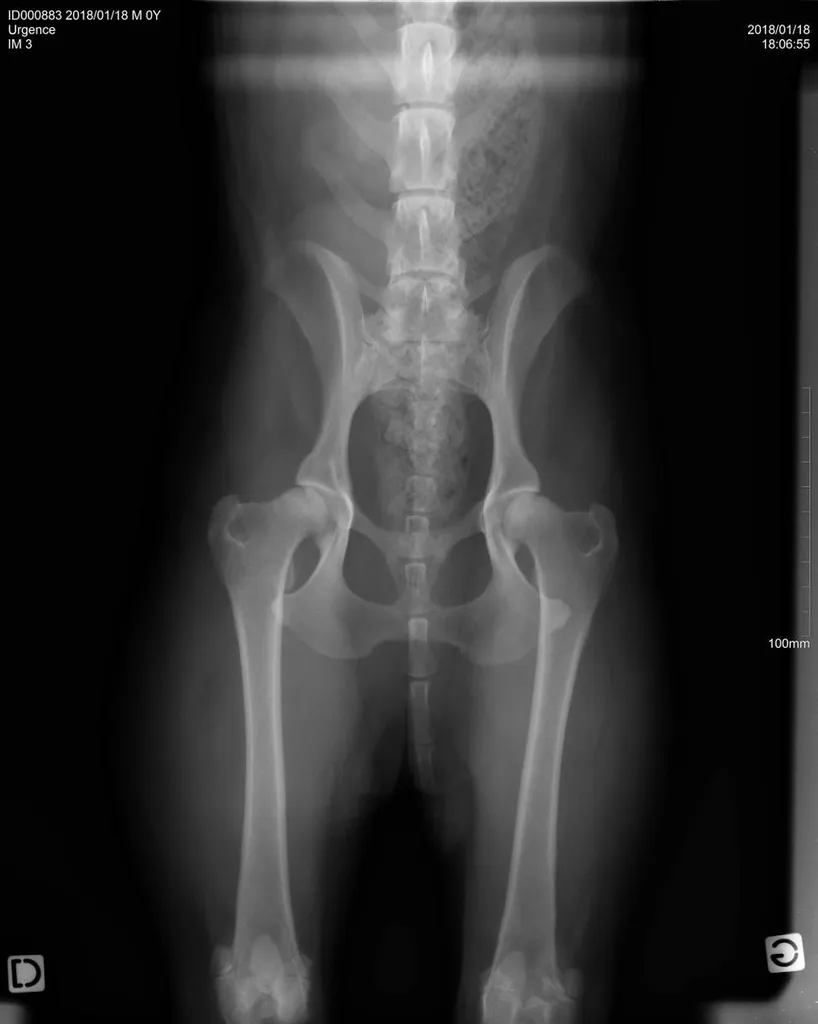

La radiographie reste indiquée dans de nombreuses affections, quelles soient respiratoires (radiographie cervicale ou thoracique), digestives (radiographie thoracique ou abdominale), locomotrices (membres, colonne), dentaires.

Certains clichés demandant des positions particulières (hanches, sinus, dents), une anesthésie peut être nécessaire afin de procéder à cet examen. La clinique vétérinaire du Las saura vous conseiller et vous avertir si cela est envisagé.

Comme tout examen, il présente ses limites. Le principe de la radiographie étant l’utilisation du contraste (visualisation d’un tissu par rapport au tissu environnant et par rapport à sa radiodensité), certaines pathologies ne peuvent être que suspectées par radiographie mais nécessite d’autres examens (échographie, endoscopie, scanner, IRM).